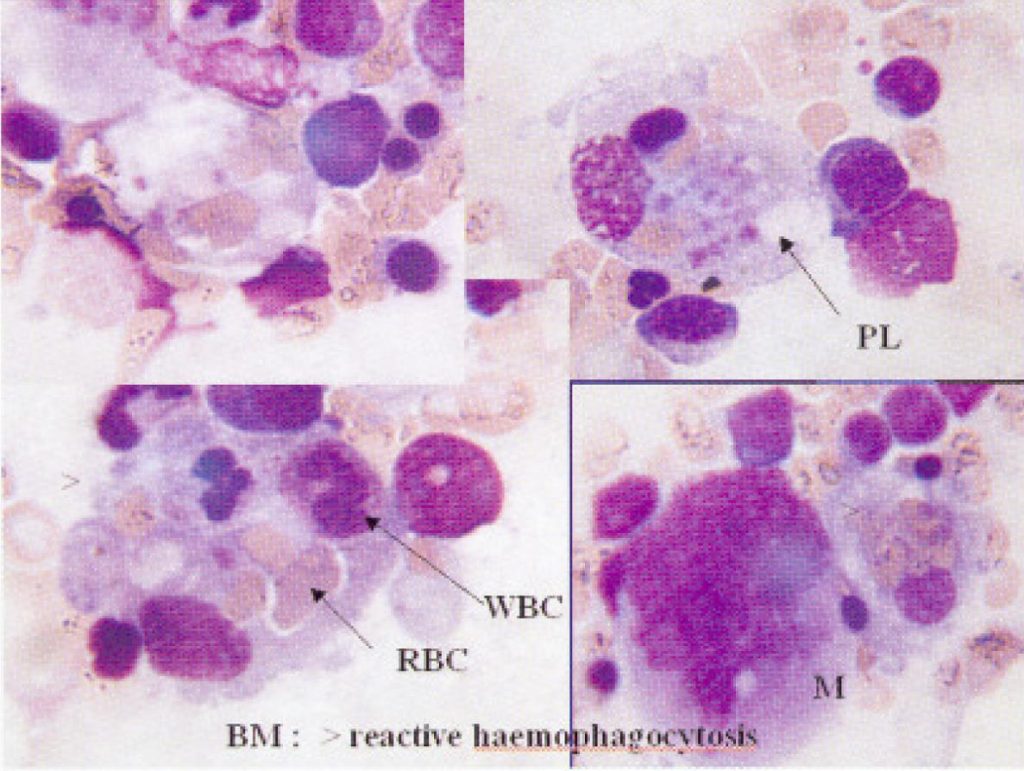

Subsequent blood test showed pancytopenia and leucoerythroblastic picture. Bone marrow examination (Fig.3) confirmed reactive hemophagocytic syndrome and trephine showed the presence of tuberculous granuloma. The condition of the patient further deteriorated and finally died despite the use of intravenous methylprednisolone.

The final diagnosis was disseminated tuberculosis with reactive hemophagocytic syndrome.

Reactive hemophagocytic syndrome is a reactive condition in which there is systemic proliferation of non-neoplastic histiocytes engaged in phagocytosis of hemopoietic cells, associated with otherwise unexplained blood cytopenia, and fever.1 The exact pathogenesis of reactive hemophagocytic syndrome remains unknown. The systemic activation of histiocytes in hemophagocytic syndrome associated with lymphoma probably occurs as a result of macrophage activating lymphokines released from neoplastic lymphocytes.2 There has been no controlled treatment trial on tuberculosis-associated hemophagocytic syndrome. The rationale for use of high dose steroid and intravenous immunoglobulin (IVIG) in those extremely severe clinical conditions is to interfere with phagocytosis and suppress lymphocyte activation. Gill et al reported 3 adult cases of hemophagocytic syndrome treated successfully with high dose IVIG alone 3, however, the optimal treatment protocol remained uncertain. There was a recently reported case of disseminated tuberculosis associated hemophagocytic syndrome and multiple organ dysfunction syndrome successfully treated by plasma exchange and continuous haemodiafiltration.4

Hemophagocytic syndrome is shown to be a cytokine-mediated disease, characterized by hypercytokinemia, as a result of an inappropriately or excessively mounted immunological reaction in susceptible hosts, giving rise to unregulated and overstimulated histiocytic proliferation resulting in up-regulated cytokine production and hemophagocytosis.